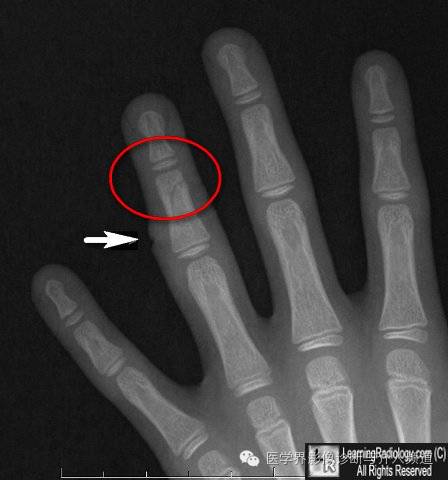

5、指骨血管沟:血管沟通常只见于骨皮质侧,呈对角线样走行。